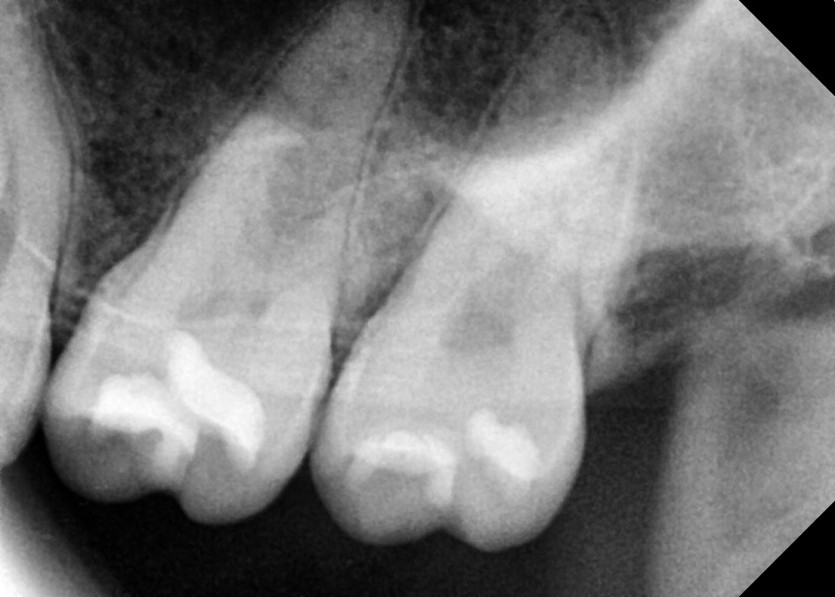

#28,38 사랑니 발치

구강 외과 전문의가 당일 발치했습니다.